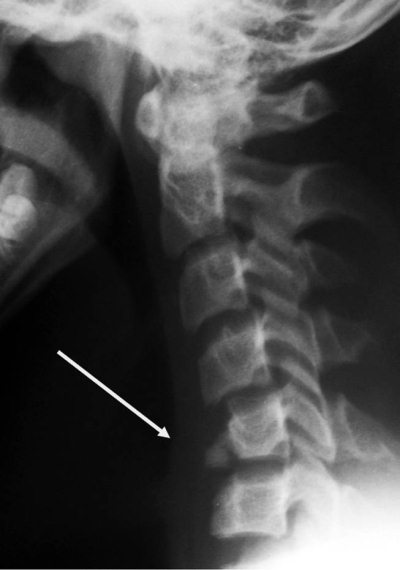

- рентгенологическое исследование – может быть выполнена как рентгеноскопия (наблюдение за проблемным участком на мониторе в режиме реального времени), так и рентгенография (при этом делают рентгенологические снимки);

Рентгенография является основным инструментальным методом исследования при подозрении на вывих шейного позвонка. При этом используются основные (прямая и боковая) и дополнительные проекции (снимки в косом положении, рентгенограммы через рот, снимки в состоянии разгибания и сгибания шеи. Рентгенография с привлечением дополнительных проекций проводится в зависимости от локализации нарушения. Метод позволяет выявить подвывих, определить его точную локализацию, установить функциональные нарушения.